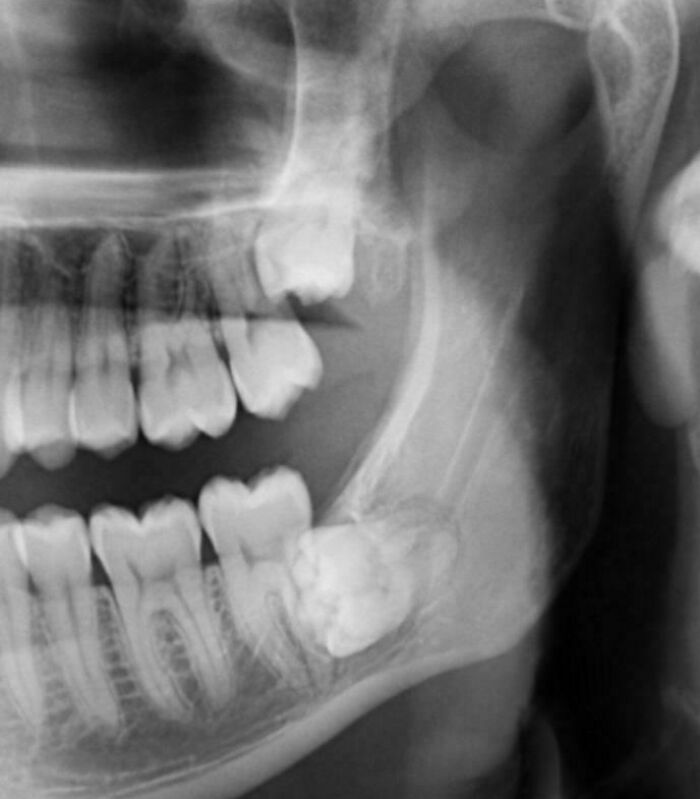

Went In For Teeth Cleaning Last Month And Mentioned A Numb Feeling In A Tooth- I Was Shocked To Find A Tumor Eating My Jaw Bone

This photo is my CT scan. Biopsy surgery results were non-cancerous, thankfully. It’s been a real WTF month.